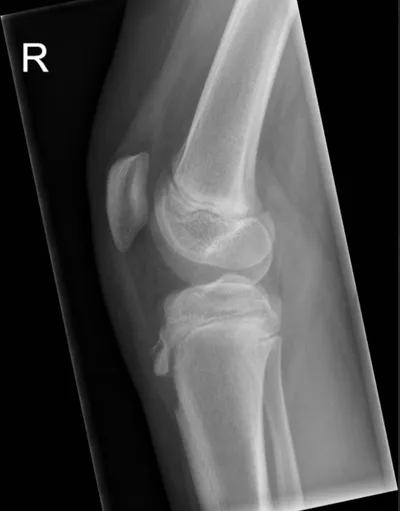

Apophysitis Radiology Images

Browse 3 medical images tagged with apophysitis. This collection includes various imaging modalities for medical education and reference.

About Apophysitis Imaging

- This collection contains 3 radiology images related to apophysitis, including various imaging modalities such as X-rays, MRIs, CT scans, and ultrasound images commonly used in medical diagnosis and education.